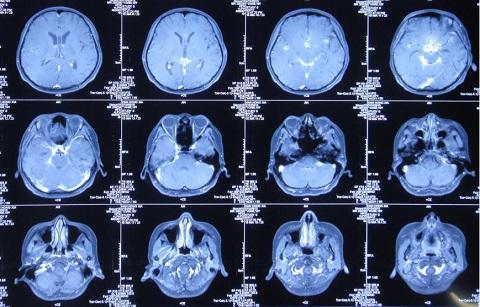

8月16日,患者脑脊液仍然色黄浑浊,复查增强MRI现实四叠体池区、鞍区、环池内多发结核脓肿。

10月18日,患者脑脊液外观基本清亮,增强头MRI现实仍然课件鞍区多发结核脓肿、四叠体池、环池内病变明显改善。

10月20日,行分流手术,术后复查增强头MRI见图。